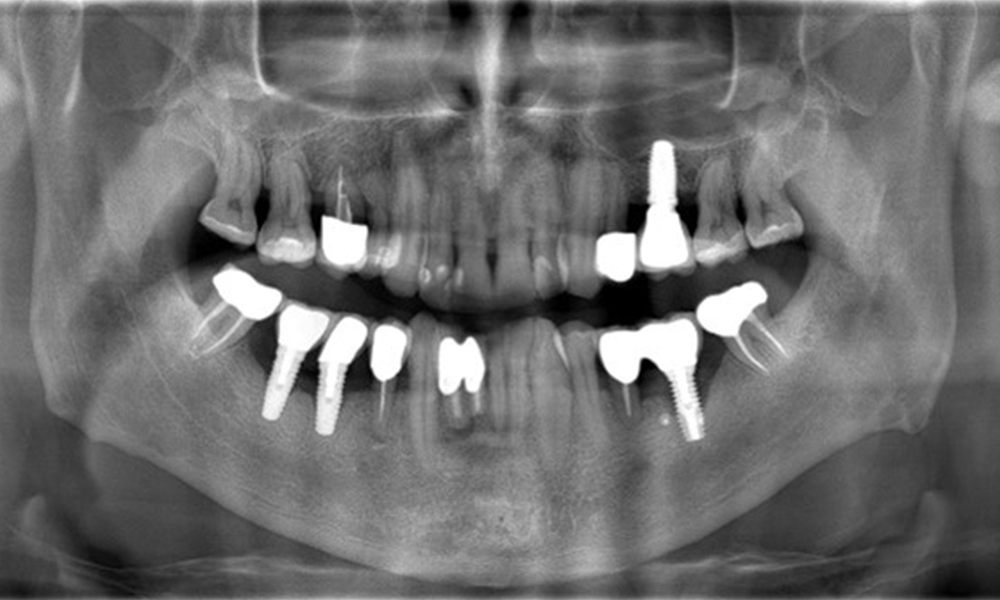

The X-ray images show the progression of bone loss.

The X-ray images show the progression of bone loss. OPG from 29.06.2020 (left) and OPG from 26.02.2024 (right).

OPG: 26/02/2024 Dental X-ray: 18/01/2024